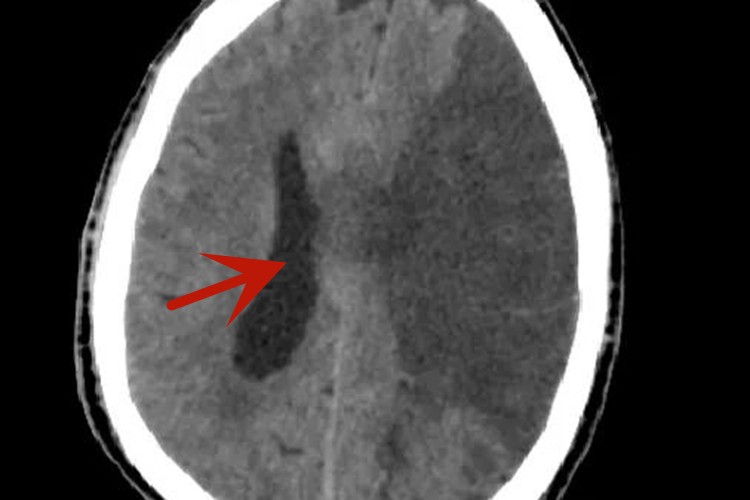

脑血栓的患者CT检查可出现低密度病灶,边界不清,随后可能会出现病灶等密度影,或者是病灶区出现增强现象。

脑血栓的患者在发病24小时后会在病灶区出现低密度影,边界不清,梗死面积大者可伴有明显的占位效应,发病后2-15天可见均匀片状或楔形的明显低密度病灶;发病第2-3周时,病灶可为等密度影,CT上难以分辨;发病5周后,大梗死病灶呈长久性的低密度影,边界清楚,无占位及增强现象。